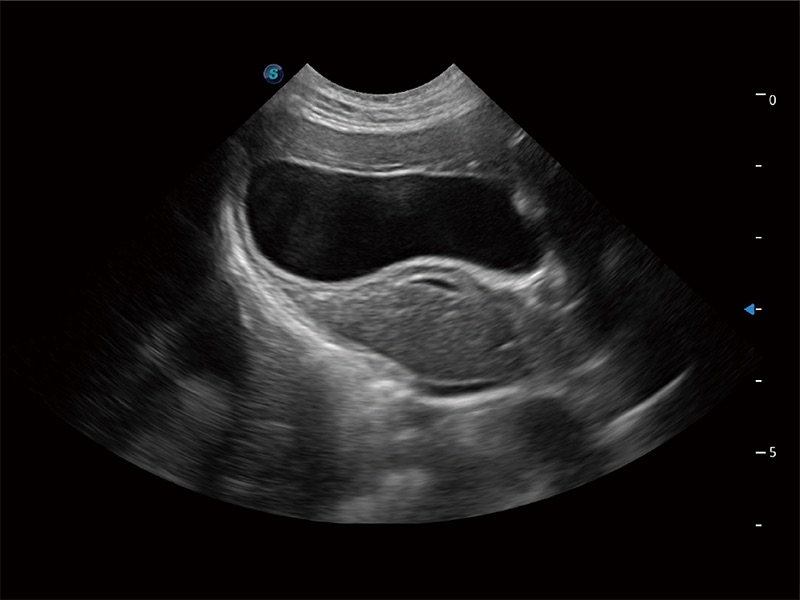

高性能和先進(jìn)的臨床應(yīng)用工具可以為動物醫(yī)生提供臨床信心。ProPet 80 搭載了先進(jìn)的腹部和淺表應(yīng)用工具,幫助醫(yī)生在日常臨床實(shí)踐中發(fā)揮前所未有的作用。

一鍵自動識別膀胱壁及自動測量膀胱容積,不受膀胱形狀和大小的限制,幫助醫(yī)生快速精準(zhǔn)獲得測量的數(shù)據(jù)。